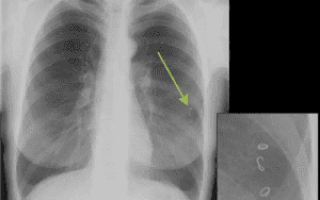

- При цистицеркозе личинка-цистицерк свиного цепня фиксируется в легочной интерстициальной ткани, и усиленно там размножается. Около нее создается фиброзная капсула, охваченная лимфоцитарной инфильтрацией, и образуются многочисленные круглые или овальные, диаметром 1 или 2 см, отдельные пузырьки. Вначале заболевания в прилегающей к очагам легочной паренхиме изменений не наблюдается, но затем развивается деформация структуры легочной ткани. Если пузырьки образуются под плеврой, то происходит очаговое уплотнение реберной и междолевой плевры. Когда же произойдет гибель цепня (через 2-3 года) очаги кальцифицируются.

Самый простой и достаточно надежный метод определения наличия паразитов в легких рентген. Рентгенографическое исследование позволяет обнаружить следы жизнедеятельности глистов, самих гельминтов, кисты, образующиеся при эхинококкозе.